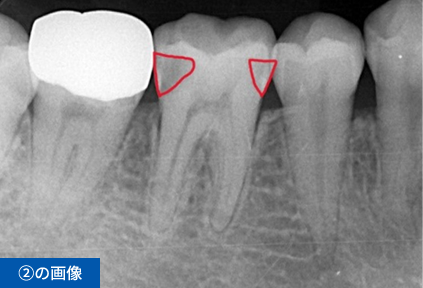

右下6番目の歯が、冷たいものがしみて痛いという主訴でご来院されました。